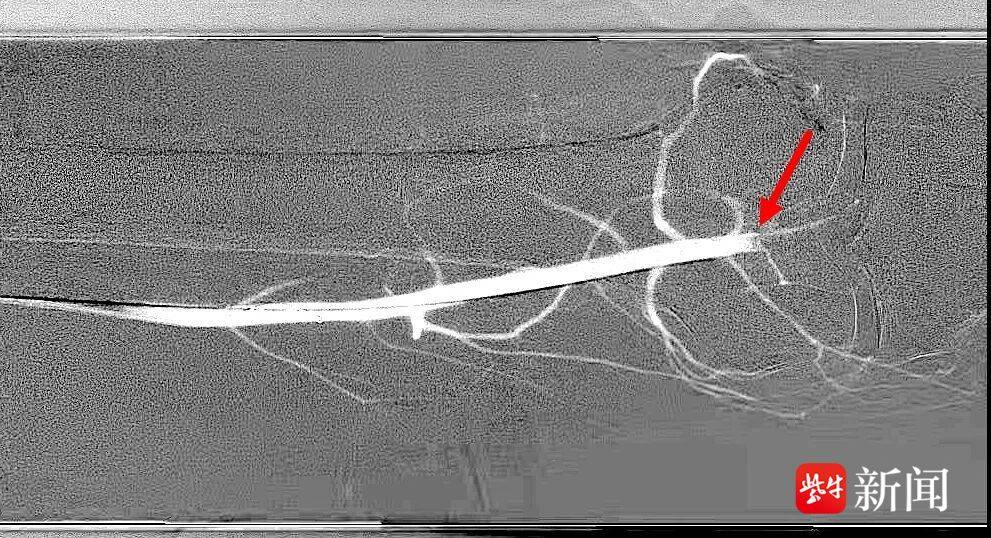

介入血管科何旭主任团队30分钟内完成造影准备,屏幕上的影像让所有人倒吸一口凉气:腘动脉断裂伴血栓形成,仅存少量侧支循环,属于Ruthford缺血分级4级——这意味着小磊的腿正在“缺血坏死”,面临截肢的风险!

血管造影

介入血管科何旭主任指着造影图像说:“目前还有少量侧支循环,说明组织还没完全坏死。如果我们能在杂交手术室一站式完成血管重建,做好并发症预防,或许还有一线生机。”